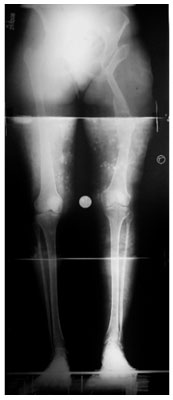

The full length x-ray after removal is showing good correction. The tibia also has some shortening, which was addressed in the 2nd stage.